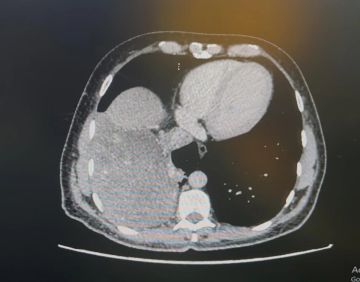

تمكّن فريق طبي متخصص في جراحة الصدر بمجمع الملك عبدالله الطبي، عضو تجمع جدة الصحي الثاني، بفضل الله، من استئصال ورم نادر وعالي الخطورة بحجم 15 سم من الجهة اليمنى لتجويف الصدر، باستخدام تقنية المنظار الجراحي، وذلك في عملية دقيقة استغرقت 4 ساعات وتكللت بالنجاح التام.تفاصيل الحالة والتشخيص

المريض، البالغ من العمر 52 عامًا، حضر إلى عيادات جراحة الصدر بالمجمع وهو يعاني من كحة مزمنة وارتفاع في درجة الحرارة. وبعد إجراء الفحوصات الطبية والأشعة المقطعية، تبيّن وجود ورم كبير يغطي النصف السفلي من تجويف الصدر، وملتصق بالفص الأوسط والسفلي من الرئة والحجاب الحاجز، إضافةً إلى ملامسته الوريد الأجوف السفلي الواقع أسفل القلب، ما جعل حالته بالغة الخطورة.خطة علاجية دقيقة وتدخل فوري